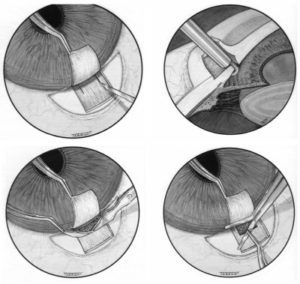

Όταν η φαρμακευτική ή η LASER θεραπεία αδυνατεί να ελέγξει την εξέλιξη του γλαυκώματος ή όταν παρατηρείται δυσανεξία ή μη συμμόρφωση στη φαρμακευτική θεραπεία προχωράμε σε χειρουργική επέμβαση.

Ποια είναι τα είδη χειρουργικών επεμβάσεων για το Γλαύκωμα;

Η πιο συχνή αντιγλαύκωματική επέμβαση είναι η τραμπεκουλεκτομή. Σ αυτήν δημιουργούμε στο άσπρο του ματιού (στο σκληρό χιτώνα) ένα καλυμμένο τούνελ που παροχετεύει το υδατοειδές υγρό από το εσωτερικό του ματιού σε μια μικρή φυσαλίδα κάτω από το άνω βλέφαρο. Έτσι ελαττώνεται η πίεση του υδατοειδούς υγρού και επομένως και η πίεση στο οπτικό νεύρο η οποία προκαλεί την απώλεια της όρασης στο γλαύκωμα.

Άλλες αντιγλαύκωματικές επεμβάσεις είναι:

Mη διατιτρένουσες επεμβάσεις

Ένθεση βαλβίδων

Κυκλοκαταστροφικές επεμβάσεις